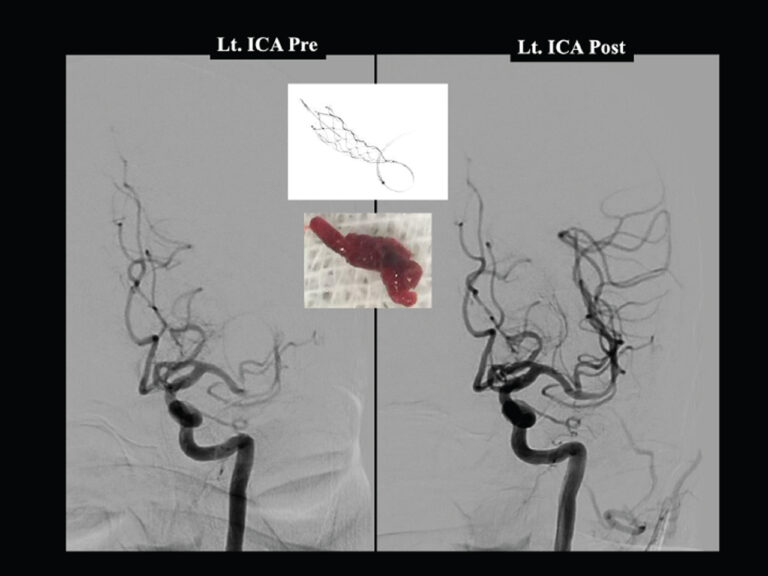

Mechanical thrombectomy involves navigating a thin catheter from an artery in the groin or wrist up to the blocked brain vessel under X-ray guidance. Devices such as stent retrievers or aspiration catheters physically remove the clot, restoring blood flow. The procedure is performed in specialized neurointerventional centers, ideally within a comprehensive stroke unit.

Modern thrombectomy achieves successful recanalization (TICI 2b/3) in 80–90% of cases in experienced centers. Complication rates are low, and the procedure significantly reduces mortality and long-term disability compared with medical therapy alone.